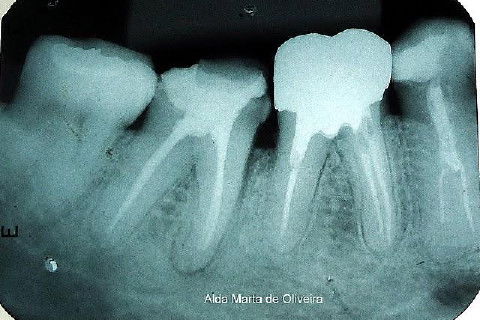

Paciente de 46 anos, encaminhado por uma colega para que eu instalasse um pino e fizesse um núcleo de preenchimento no dente 47.